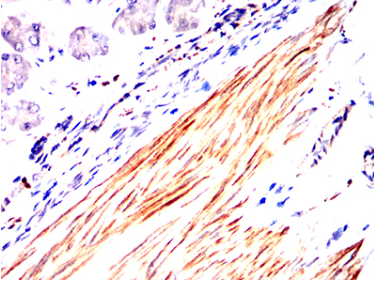

| AC1029 | ACTA2 Mouse Monoclonal antibody[1H8B8] | 100ug | $367 | 10days |

| AC1029 | ACTA2 Mouse Monoclonal antibody[1H8B8] | 200ug | $660.6 | 10days |